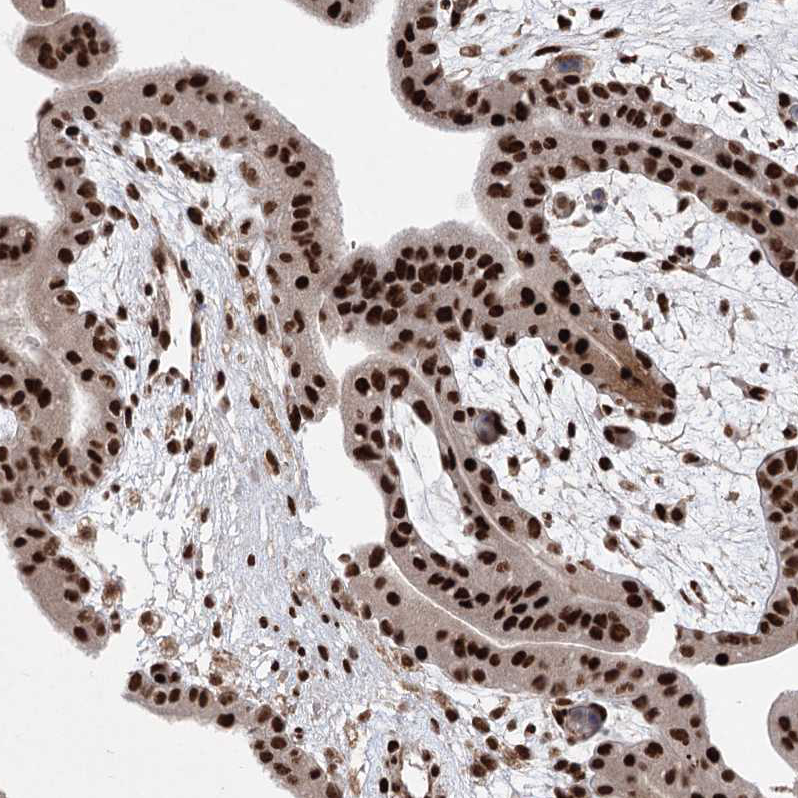

Immunohistochemical staining of human bone marrow shows strong nuclear positivity in hematopoietic cells.